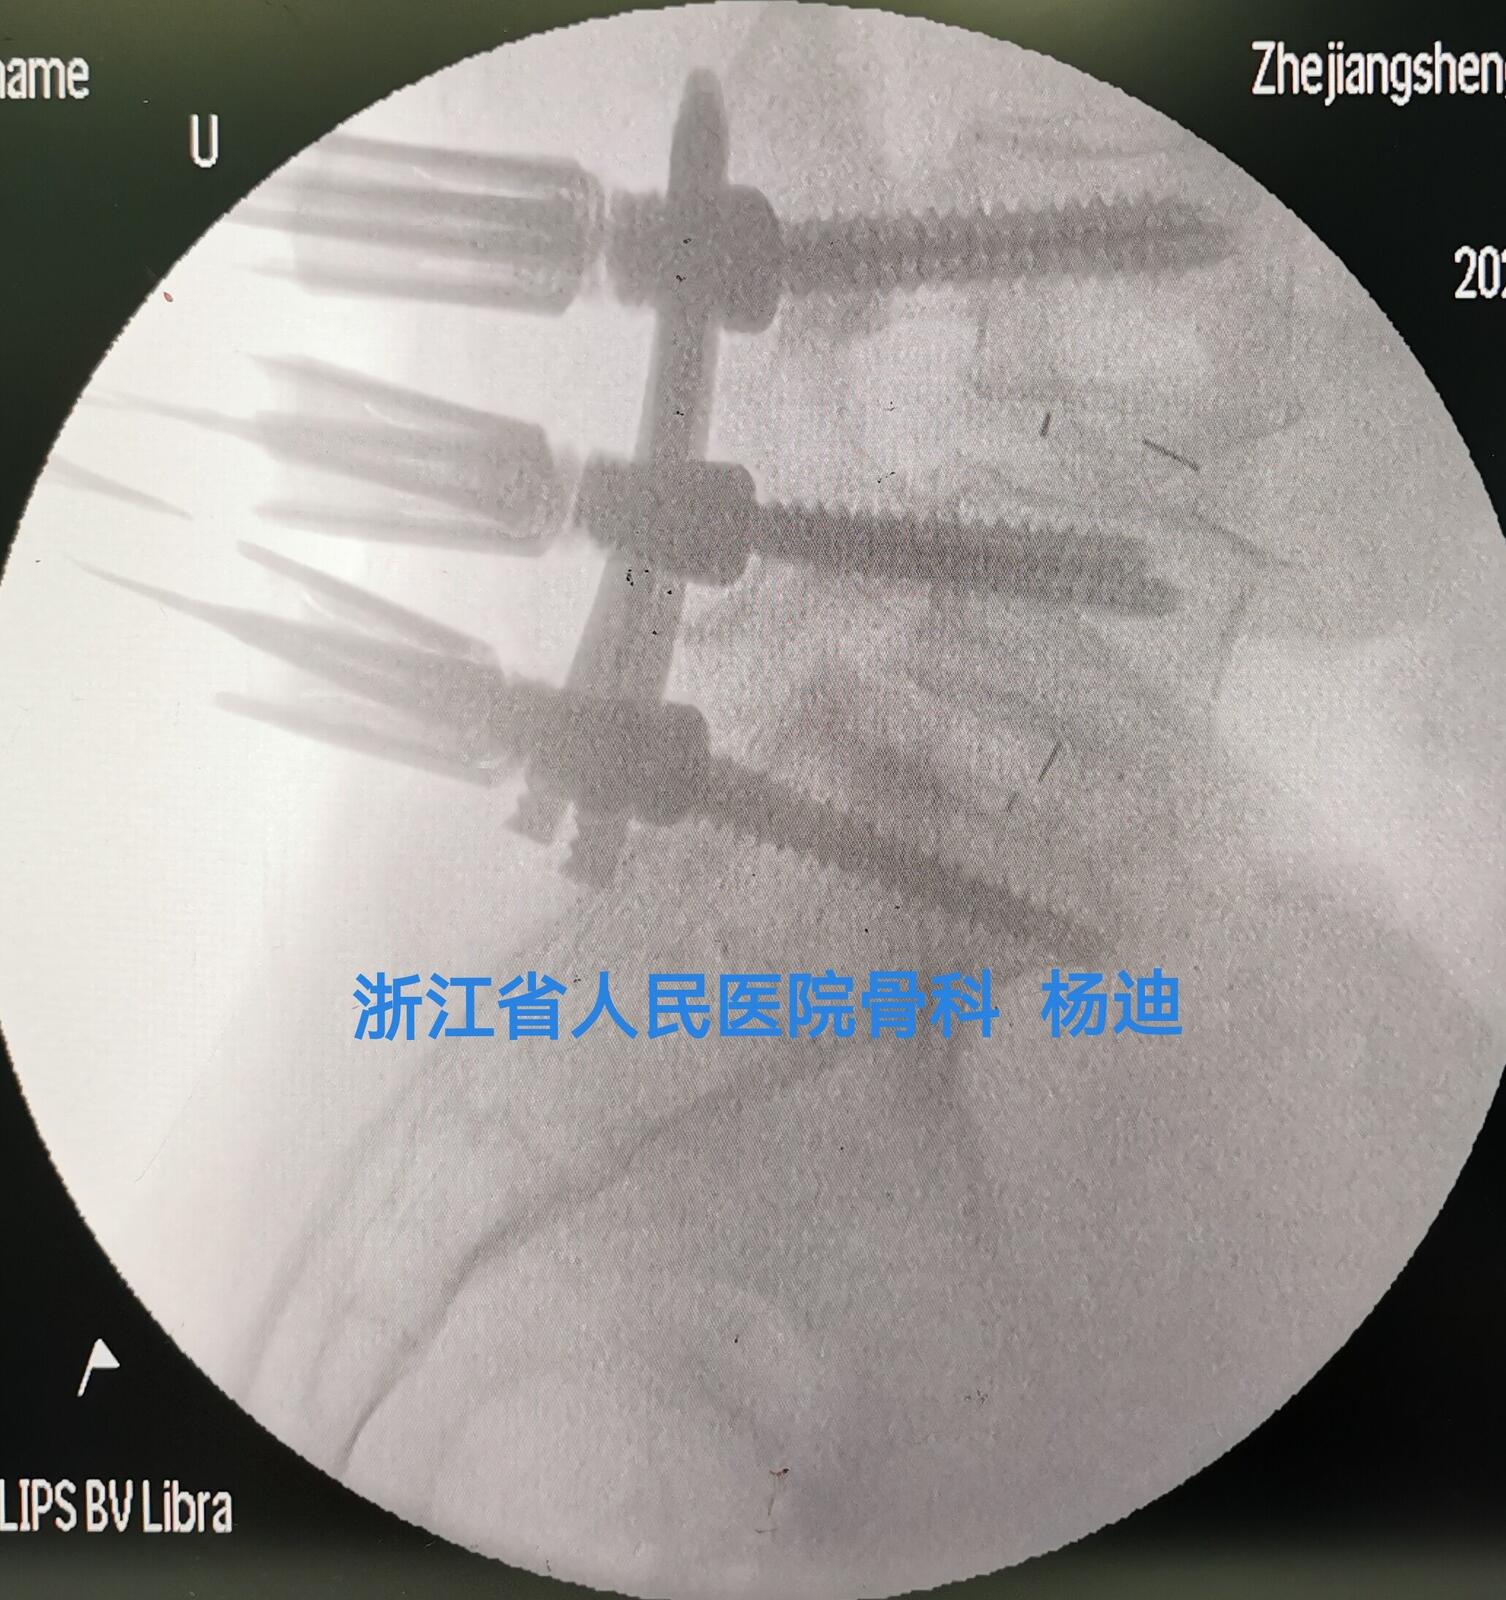

图为双侧连接棒经皮置入后,C臂透视见融合器及螺钉位置、长度满意。